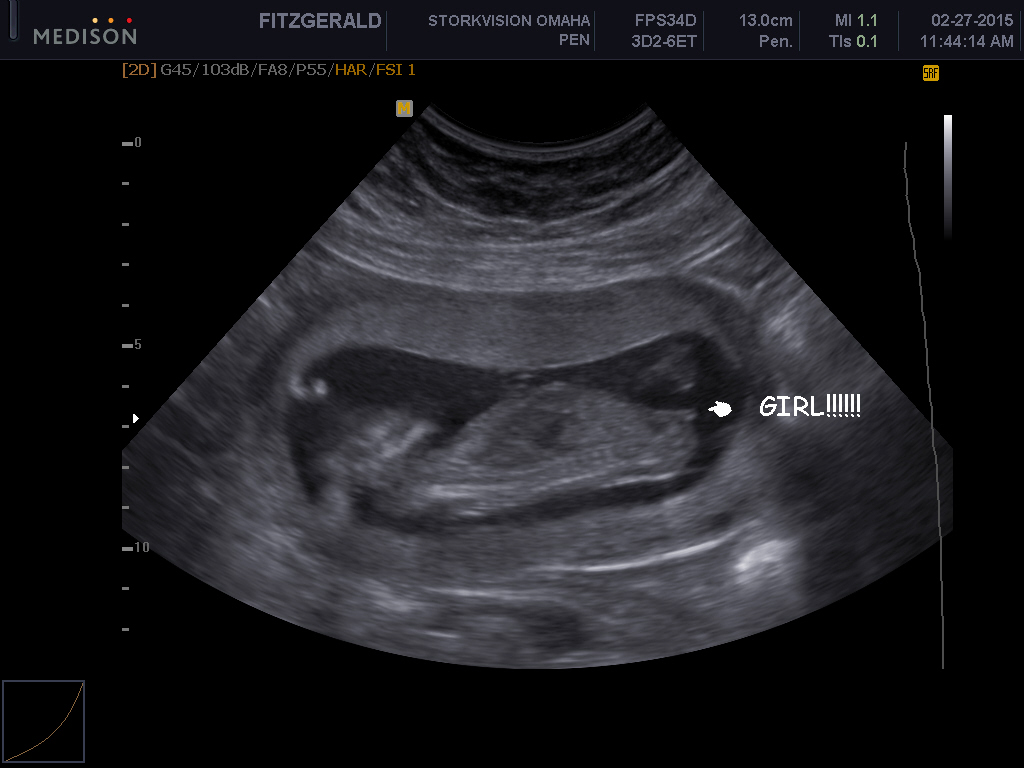

Attachment 23962Attachment 23963

Yes, girl.

Thanks! I didnt realize I pt the pic that said the gender. Oops!

Girl!

Looks girly, congrats! How far along were you? x

16 weeks